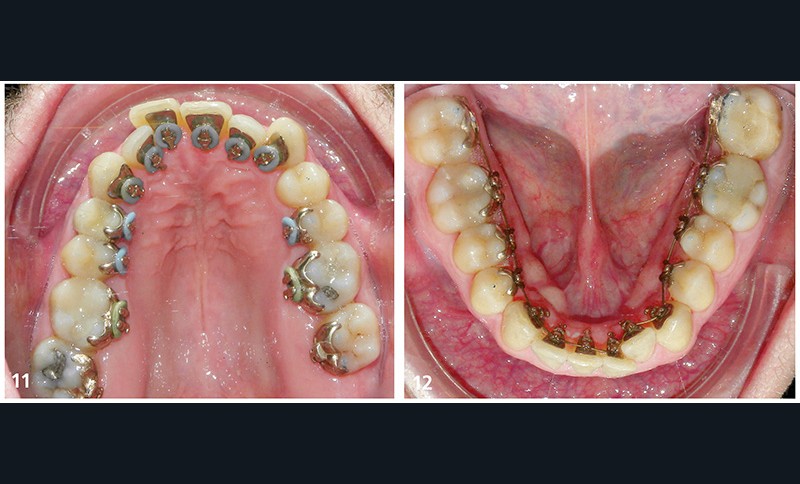

Il présente une malocclusion de classe II subdivison gauche totale par mésioposition du secteur 2 avec une déviation dentaire du milieu maxillaire à droite (fig. 2 à 6) dans un visage équilibré (fig. 7 et 8).

La mésioposition du secteur 2 a entraîné un encombrement antérieur avec malpositions des incisives supérieures, la 12 étant en occlusion traumatogène, en bout à bout avec son antagoniste (fig. 3). Dans le sens transversal, il existe une endoalvéolie maxillaire avec occlusion inversée postérieure à gauche. À l’arcade mandibulaire, l’encombrement est modéré (fig. 6).